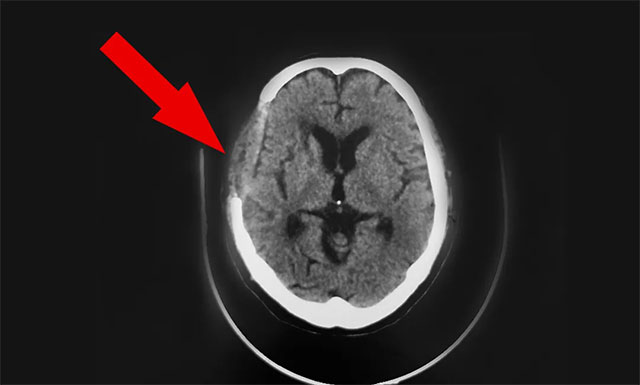

9月25日,在征得病患家屬同意下,潘仁龍醫(yī)療團(tuán)隊(duì)為病患胡某在全麻下行顳肌貼敷術(shù)。

在潘仁龍主任指導(dǎo)下,由留德博士吳治群醫(yī)生主刀,黃秀夫醫(yī)生I助,經(jīng)過近六小時(shí)手術(shù)順利完成,圍手術(shù)期并發(fā)癥:無;病理標(biāo)本:無;50毫升失血量/未輸血。

手術(shù)后一天,患者胡某蘇醒,頭腦清醒,并能下地走動(dòng)。

▲ 手術(shù)后

10月8日,雙節(jié)的最后一天,患者神志清,精神佳,眼球各向活動(dòng)好,伸舌居中,張口、鼓腮、吹起動(dòng)作可,雙肺呼吸音清,四肢肌張力正常,雙側(cè)巴氏征未引出;诨颊呋謴(fù)可,予以辦理出院。